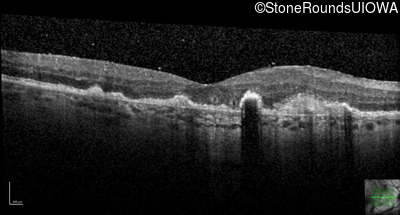

Malattia Leventinese (IIJ)

Malattia Leventinese (IIJ)

This 43 year old woman has experienced a gradual reduction in her central vision for the past 3 years.

| Malattia Leventinese | EFEMP1 | Arg345Trp CGG>TGG | AD |